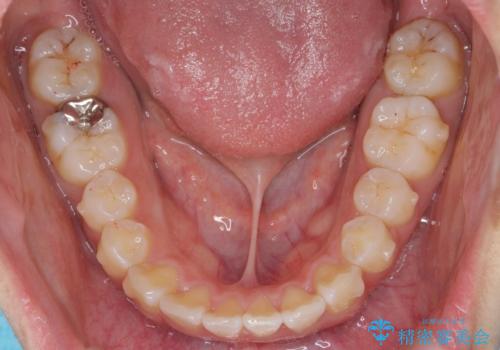

- 前歯の目立つねじれを矯正治療で治したい、と来院されました。

マウスピース矯正を始める前に、ねじれを取るのが短期間で済む部分ワイヤー小矯正を行うことで、全体的な治療期間を短くする治療計画を実行していきます。

前歯のねじれはマウスピース矯正の苦手な動きになり、治療期間が長くなる原因になりやすいです。